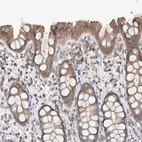

Immunohistochemical staining of human lymphoid tissues shows strong cytoplasmic positivity in lymphoid cells.